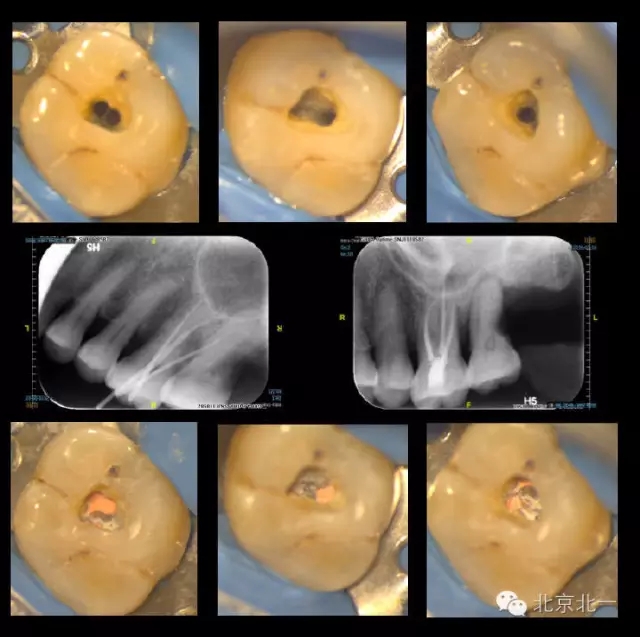

再看我們的現(xiàn)實(shí),在我們的日常工作中,也一直期望能對(duì)微創(chuàng)開髓多有嘗試,可惜的是由于我國患者的口腔保健意識(shí)還有待提高,很多來牙髓病??凭驮\的患者牙體本身由于病變已沒有微創(chuàng)的可能。前段時(shí)間終于等到了這么一例牙周牙髓聯(lián)合病變,患者有著強(qiáng)烈的保留牙齒的愿望,但在牙周治療中并發(fā)了牙髓炎的癥狀,因此轉(zhuǎn)診至牙體牙髓??菩枰M(jìn)行根管治療。

對(duì)于這個(gè)冠部牙體組織完好的病例,我們也確實(shí)想給她盡量保留健康組織,于是就開始了對(duì)這個(gè)病例的微創(chuàng)治療。

根充完成后,用樹脂對(duì)牙齒進(jìn)行了充填(由于是急診患者,很遺憾忘了拍攝術(shù)前照)。